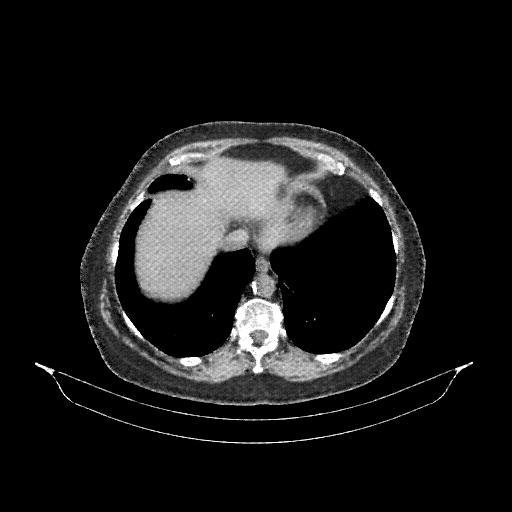

Generated VENOUS CT scan (A→B translation)

No window - Raw intensity values

Lung window (WL -600, WW 1500 β†’ Low βˆ’1350, High +150)

Mediastinum window (WL 40, WW 400 β†’ Low βˆ’160, High +240)